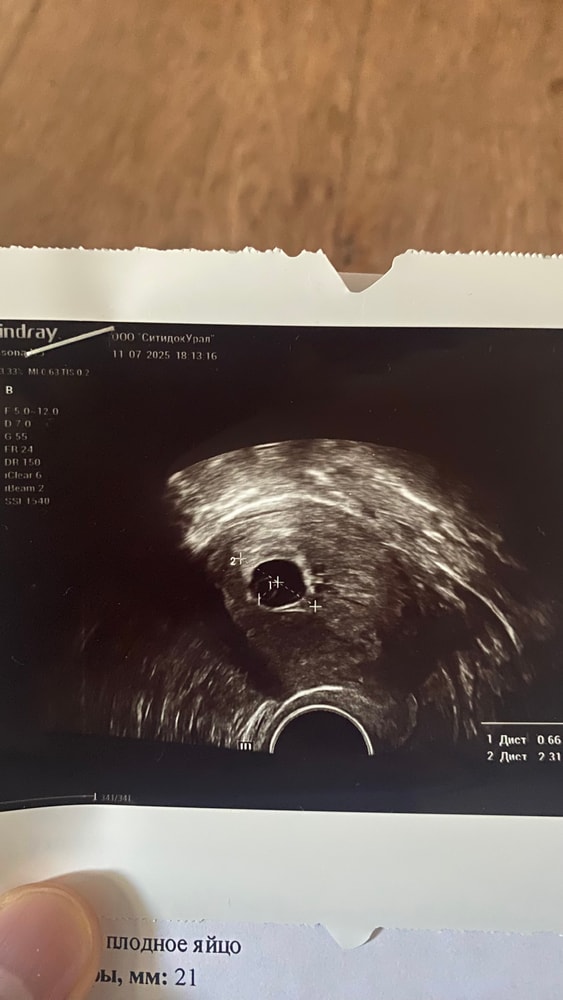

29 лет. Первая беременность. 30.06 была на узи ПЯ 7.2мм, ЖМ 1.4мм,эмбрион не визуализируется. 03.07 ПЯ 11мм, ЖМ 2.2мм, эмбрион не визуализируется. 11.07 ПЯ 21мм, эмбрион не визуализируется. Про размеры ЖМ ничего не написали, делала в др клинике. Просто сказала , что ЖМ есть и посоветовала подождать ещё неделю. Есть ли смысл ждать? Вряд ли за неделю что то появится если при размере 21мм в ПЯ пусто. Цикл у меня не стабильный от 42 до 53 дней. Может ли быть что была поздняя овуляция и эмбрион появится позже ? Прикладываю так же фото последнего узи